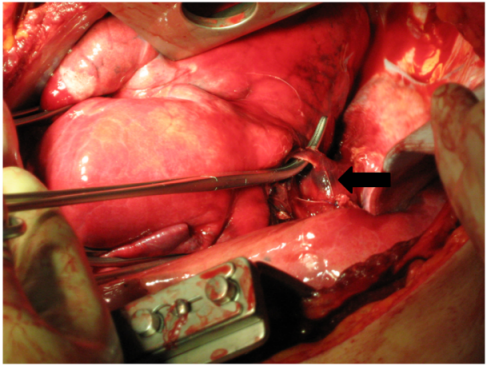

Upon arrival at the emergency trauma room a blood-soaked dressing showed. Through the drainage one liter of blood emerged and the bleeding was persisting (Figure 1 [Fig. 1]). Despite of pressure infusion of two red cell concentrates and several liters of ringer’s solution circulation could not be improved. That is why the patient was transferred to the operating room. During intubation with a double-lumen tube the blood pressure decreased and ventilation of the patient became difficult. On suspicion of a spontaneous tension pneumothorax on the left side (auscultatory breathing sounds only on the right side) a drainage was placed immediately in the second intercostal space on the left side (28 Ch). Air and blood emerged explosively through this drainage. After that, blood pressure increased and the ventilation improved (decrease in ventilation pressure). Simultaneously, sonography of thorax and abdomen was performed to exclude pericardial tamponade and intraabdominal bleeding. After left-lateral thoracotomy in the 5th intercostal space there was a pleural cavity filled with clots of blood and a multiple perforated superior lobe with multiple contusions could be seen. From the shot hole blood poured massively. Additionally, a sagittal through-and-through wound in the inferior lobe and a shotgun pellet in the main stem of the pulmonary artery showed (Figure 2 [Fig. 2]). For bleeding control and prevention of pulmonary embolism the hilum, of the lung was immediately disconnected and suction was performed via cell saver. Because of the persistent diffuse bleeding, the pleural cavity was plugged temporarily with operating cloths. After quick resection of the superior lobe and release of the clamp on the hilum of the lung, the specific disconnection of the inferior lobe followed. The big shot channel was opened via linear cutter (“tractotomy”) and open vessels and bronchial tubes were ligated. Smaller superficial lesions could be sealed by argon beamer. The removal of the shotgun pellet from the pulmonary artery required a brief disconnection with following sewing-over with felt-laminated sutures. After removal of additional shotgun pellets from the hemorrhagic dorsal wall of the thoracic cavity, the prophylactic incision of the pericardium followed to exclude a lesion of the heart.

Figure 1: Tamponade and drainage of the left chest